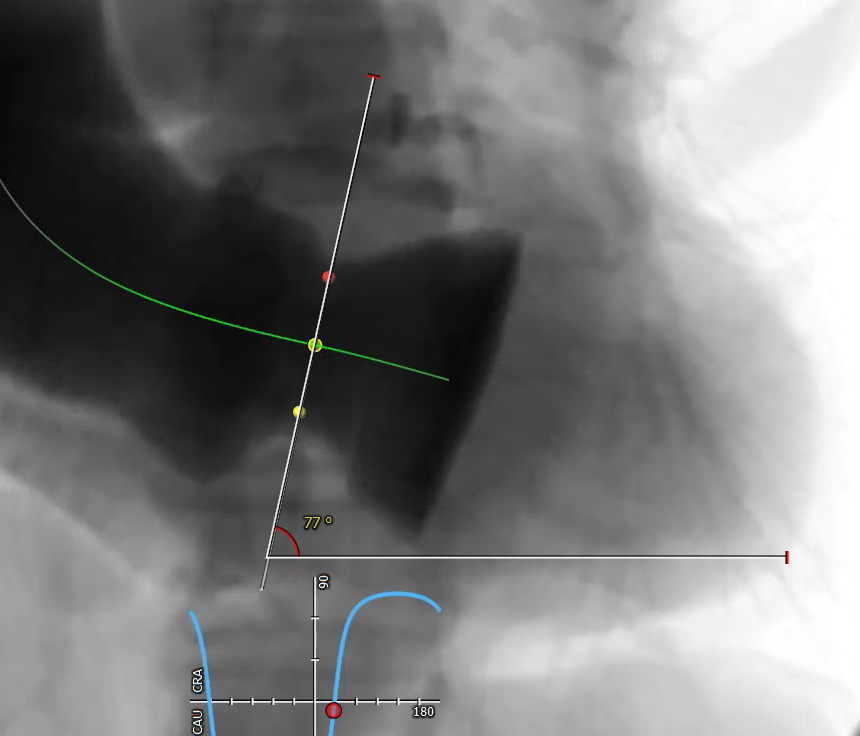

患者瓣膜结构为三叶瓣,无明显增厚和钙化,法式窦结构,双侧冠脉开口高度可。升主动脉增宽,主动脉根部角度78°。主动脉瓣环周径78.8 mm,面积487.9 mm²,平均直径25.1 mm;左冠高度14.7 mm,右冠高度14.7 mm;左室流出道周径26.0 mm,主动脉窦管交界处(STJ)高37.5 mm。

患者年龄较大,主动脉瓣单纯关闭不全,瓣膜锚定难度高,且该病例为典型的“横位心”,瓣膜释放空间较小。与王坚刚、李岩、王胜询、郑帅、孟斐、张春晓教授会诊讨论后,张海波教授团队决定利用3D打印技术,选择27#Ken-Valve瓣膜完成此次手术。

张海波教授:此病例为单纯的主动脉瓣关闭不全患者。CT分析提示,主动脉根部角度为78°,为重度“横位心”患者,给瓣膜的植入带来了巨大的挑战。术中采用了Ken-Valve输送系统,进入左心室后进行调弯,减少了对升主动脉的影响,从而增加了瓣环上的操作空间,保证了瓣膜的同轴性,整个手术过程十分顺畅。对于重度横位心、单纯主动脉瓣关闭不全的病例,这是难能可贵的。术后即刻患者反流消失,结果令人满意。由于Ken-Valve瓣膜具有独特的定位件及裙边设计,其他长支架自展瓣难以企及。